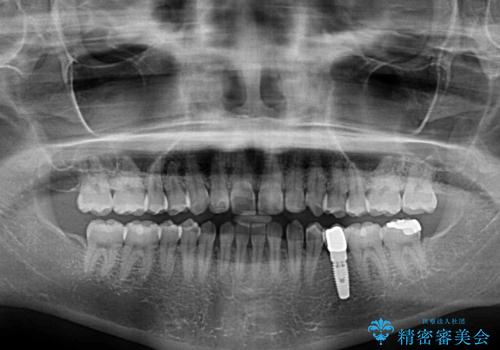

- 大きすぎる上顎前歯と、隙間の空いた下顎歯列を気にして来院された患者様です。

上顎前歯にはセラミッククラウンが装着されており、顔や他の歯と比較して幅の大きい状態でした。

下顎前歯は空隙歯列弓であったので、アンカースクリューとワイヤー装置を用いてスペースを閉じていくこととし、上顎前歯は矯正治療用の仮歯に置き換えた上で、仮歯の大きさを削って小さくしながら、上下前歯部の部分矯正を行うこととしました。